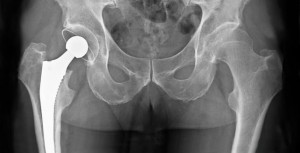

¿Cuánto tiempo dura un reemplazo de cadera? ¿Y el de rodilla?

De acuerdo a lo observado en grandes registros nacionales, puede esperarse que el 58% de los reemplazos de cadera y el 82% de los de rodilla duren 25 años.The Lancet, 16 de febrero de 2019